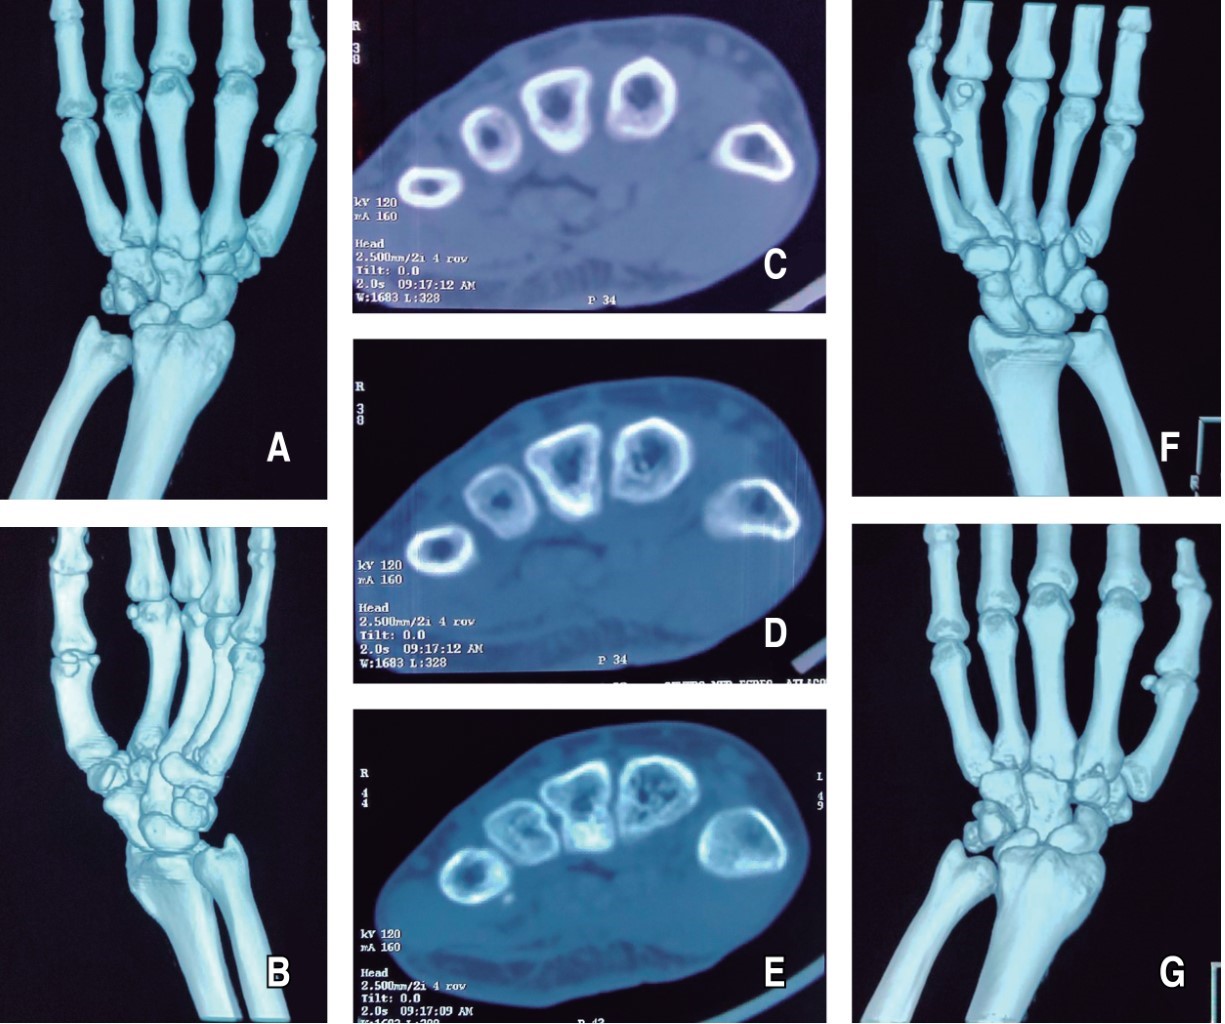

Radiográficamente sin datos de solución de continuidad, pero con pérdida de la congruencia articular de la base del cuarto y quinto metacarpiano no reciente, por lo que se solicita tomografía axial computarizada (TAC) simple donde se corrobora luxación aislada de la base del cuarto y quinto metacarpiano de la mano izquierda con desplazamiento dorsal (Figura 2).

Figura 2